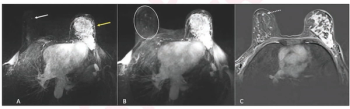

An artificial intelligence algorithm for dynamic contrast-enhanced breast MRI offered a 93.9 percent AUC for breast cancer detection, and a 92.3 percent sensitivity in BI-RADS 3 cases, according to new research presented at the Society for Breast Imaging (SBI) conference.